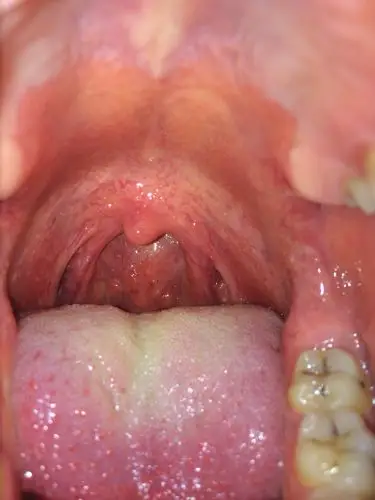

咽夹左侧那是什么东西像肿物似的,孩子没有什么感觉,以前嗓子发炎那个

舌根部淋巴滤泡增生,粘膜充血,会厌抬举可,左侧声带我太难受了咽后壁

咽口水咽后壁酸痛,求医生解答下